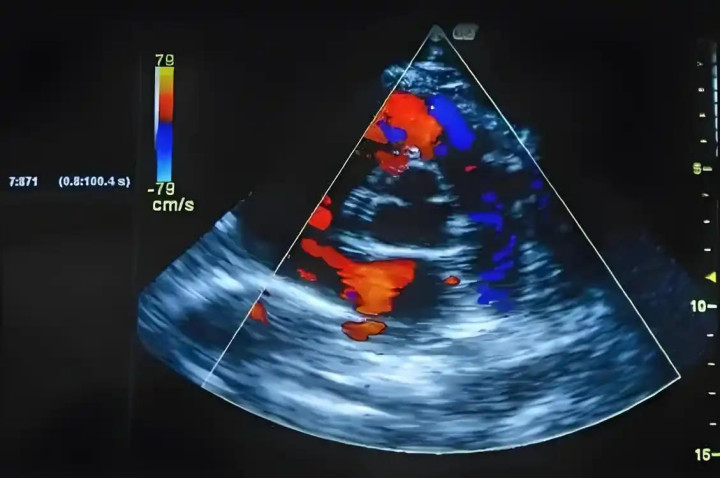

这就说到了第二个检查重点:心脏彩超(心脏B超)。

高血压时间一久,心脏为了“顶住血压”,会逐渐变厚。尤其是左心室,慢慢就像练出“肌肉”一样。听着挺厉害,其实这是“病态的肥大”。

心室肥大时间长了,会影响心脏泵血,容易导致心衰、心律不齐,甚至突然晕倒。

而这个变化,平时抽血、听诊都看不出来,只有通过心脏彩超才能看到个大概。

很多人会说:“我血压控制得还行,不用查吧?”其实有些人虽然血压不高,但心脏已经在受累了。这种“假平稳”更危险。

医生建议:高血压患者每年做一次心脏彩超,尤其是超过50岁的人群,不能省。